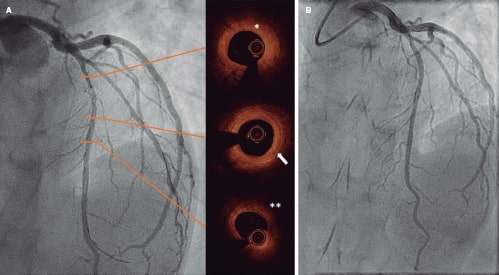

En 2014, un varón de 25 años con antecedentes de síndrome hipereosinofílico fue derivado a nuestro centro tras un hallazgo incidental de calcificación en la coronaria derecha (CD) en la tomografía computarizada. La coronariografía reveló la presencia de lesiones aneurismáticas en la CD (figura 1) y las imágenes de la OCT, la presencia de anomalías mixtas en la pared arterial: un aneurisma calcificado (figura 1A), engrosamiento intimal fibrótico, rotura de la túnica media y vasa vasorum prominentes (figura 1B), calcificación (figura 1C) y un vaso distal menos comprometido (figura 1D). Se optó por un curso diario de 100 mg de ácido acetilsalicílico.

Figura 1.

En 2024, se realizó una nueva coronariografía debido a una angina de esfuerzo que confirmó el avance de la enfermedad en la CD y una mayor calcificación en la parte media de la misma, según evidenció la OCT realizada en el mismo segmento arterial. Además, el segmento distal confirmó el avance de la enfermedad con engrosamiento intimal y rotura de la túnica media (figura 1; figuras 1E-H). El hallazgo de una nueva estenosis crítica en la descendente anterior propició que se biopsiara un segmento aneurismático de la arteria temporal (figura 2). Los hallazgos histopatológicos fueron similares a los observados en el OCT de las coronarias. La pared arterial engrosada evidenció la presencia de hiperplasia intimal fibrótica/miofibroblástica, infiltrado inflamatorio agudo, necrosis y cambios fibrinoides (figura 2A, flecha) y una pérdida de la lámina elástica interna (figura 2B, flecha; figura 2A, asterisco) y vasos adventicios, lo cual confirmó la presencia de inflamación crónica perivascular.

Teniendo en cuenta los síntomas y hallazgos en la descendente anterior (engrosamiento intimal y rotura de la túnica media, sugestivos de vasculitis; figura 3A, asterisco y flecha) y la presencia de un vaso distal sano (figura 3A, doble asterisco), se optó por realizar una intervención coronaria trastorácica con balón farmacoactivo (figura 3B).